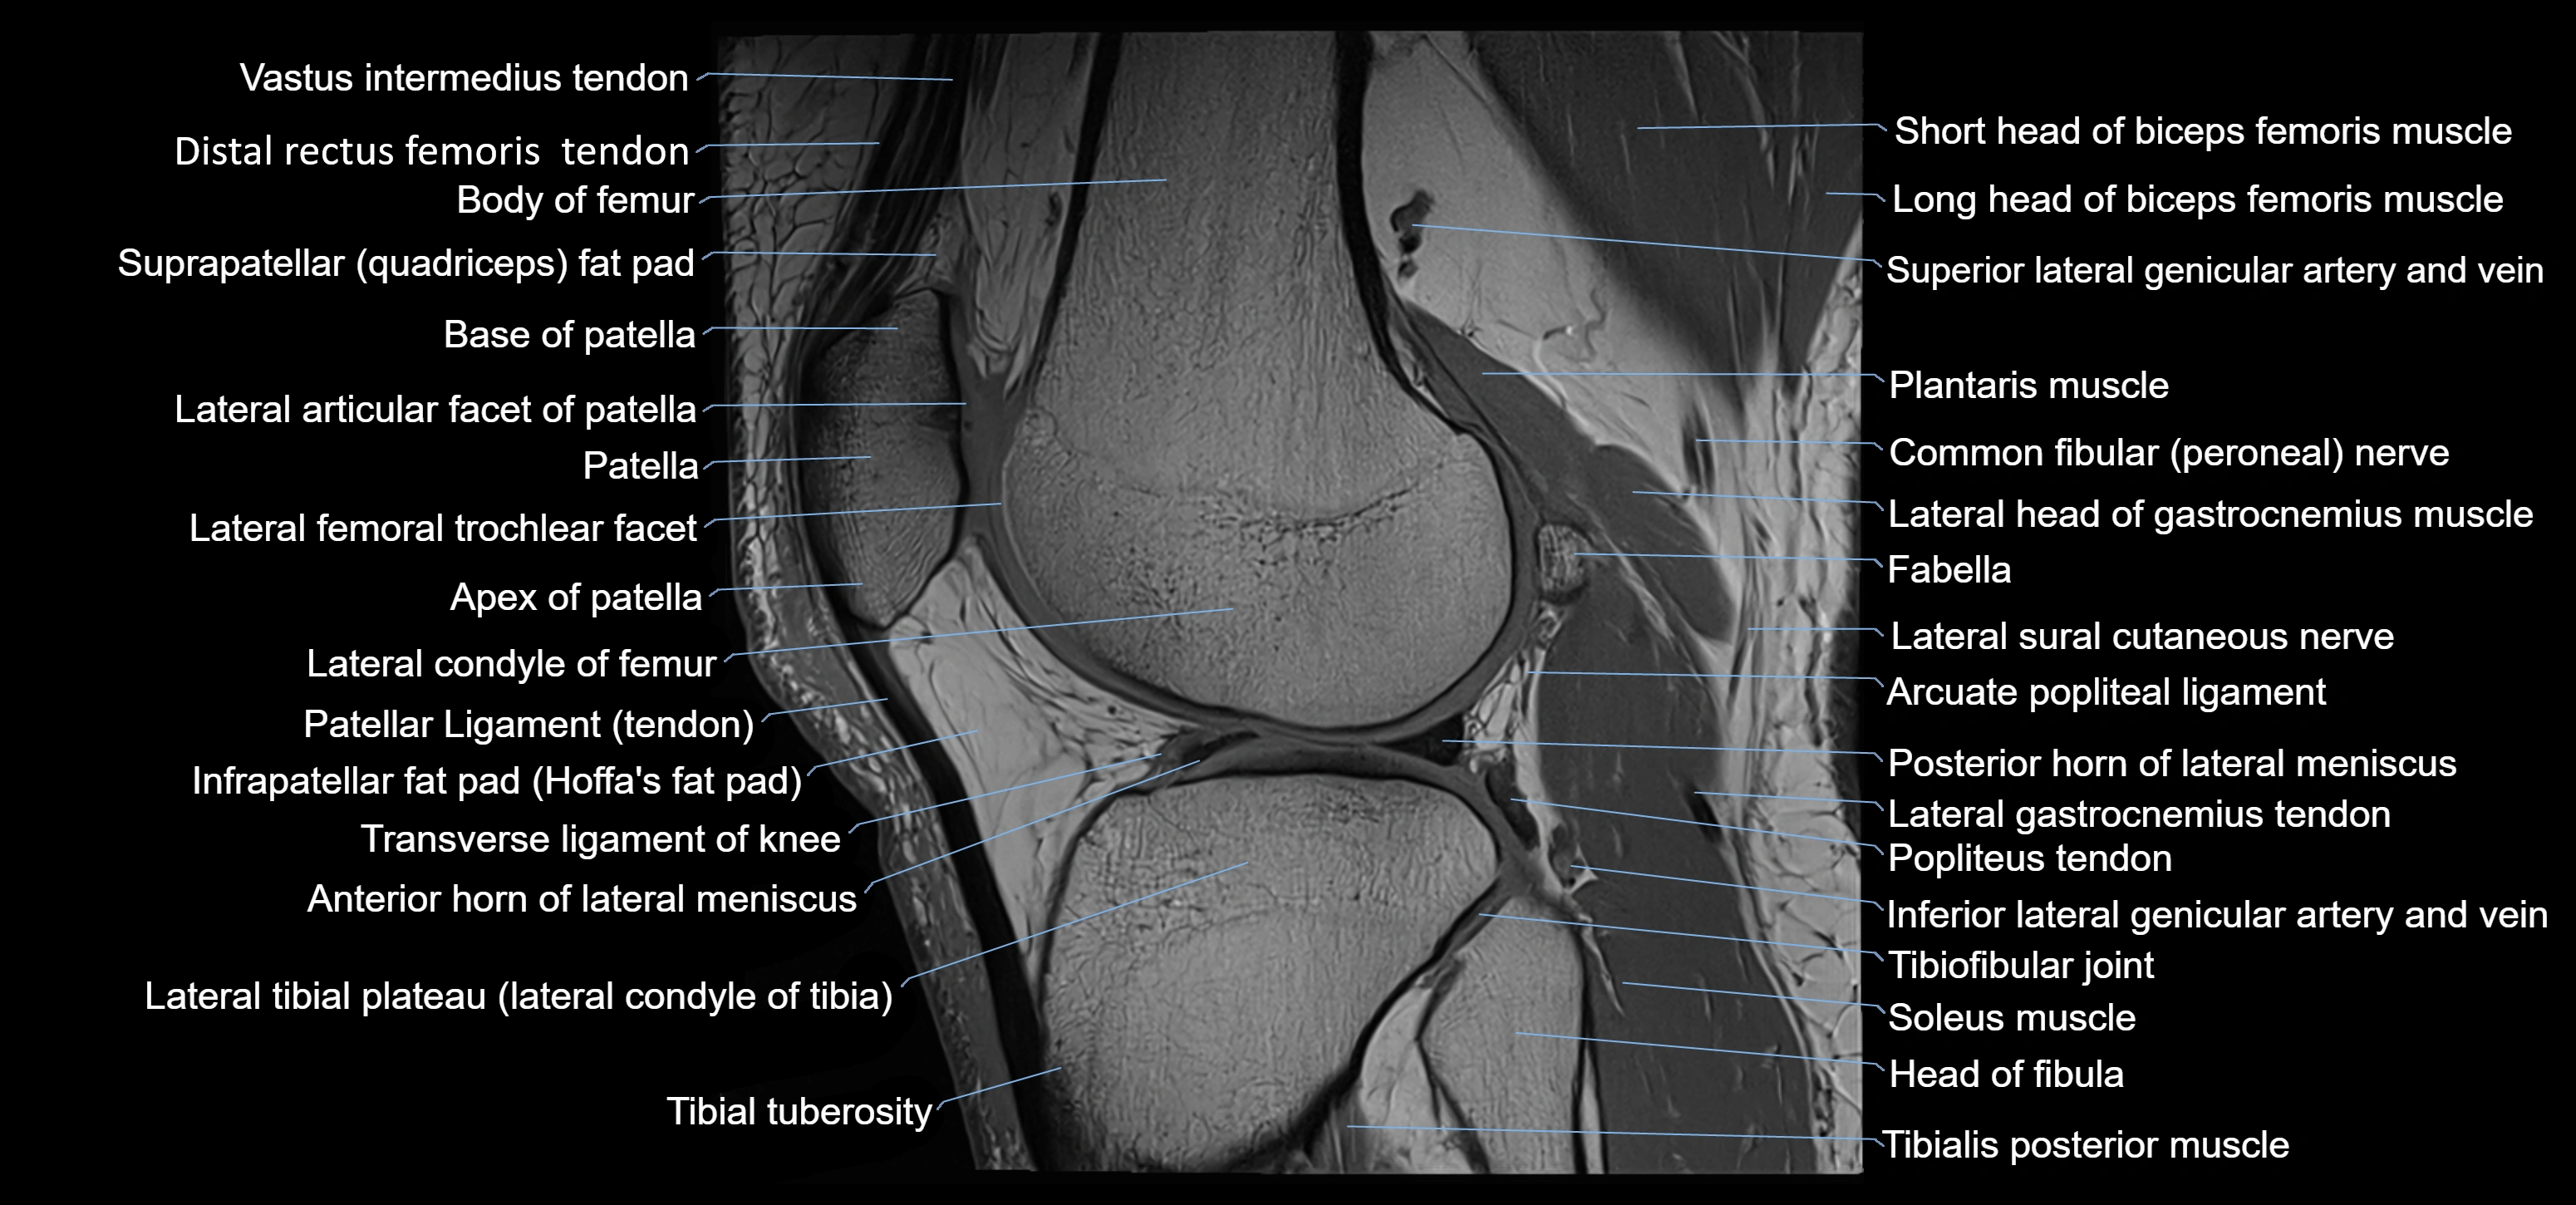

- Anterior horn of lateral meniscus

- Anterior root of lateral meniscus

- Apex of patella

- Arcuate popliteal ligament

- Base of patella

- Body of femur

- Distal quadriceps femoris tendon

- Distal rectus femoris tendon

- Distal vastus intermedius tendon

- Head of fibula

- Inferior lateral genicular artery

- Inferior lateral genicular vein

- Infrapatellar fat pad

- Lateral articular facet of patella

- Lateral condyle of femur

- Lateral condyle of tibia

- Lateral gastrocnemius tendon

- Lateral head of gastrocnemius muscle

- Lateral intercondylar tubercle

- Lateral meniscus

- Lateral tibial plateau

- Neck of fibula

- Patellar tendon (patellar ligament)

- Plantaris muscle

- Popliteus tendon

- Posterior horn of lateral meniscus

- Posterior root of lateral meniscus

- Soleus muscle

- Superior lateral genicular artery

- Superior lateral genicular vein

- Superior tibiofibular joint

- Suprapatellar fat pad

- Tibial tuberosity

- Tibialis anterior muscle

- Tibiofibular joint (proximal)

- Trochlear groove